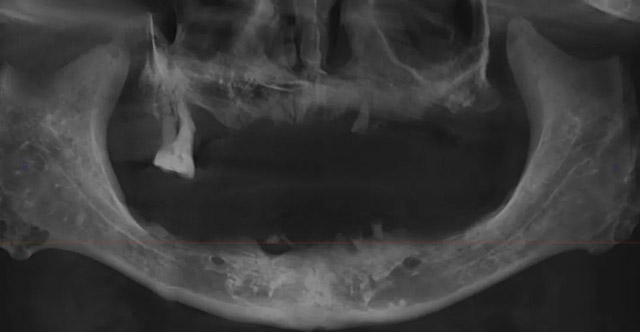

前年,杨开明发现仅存的两颗大牙中有一颗出现了松动,“我在想,如果睡觉的时候这个牙掉下来了,万一掉进我的气管就很危险了!”他去医院拔了牙,又将就用了一年多。去年,最后一颗大牙也变得摇摇欲坠,原来的活动义齿无法继续使用了,杨开明早就听闻现在有更新、更好的技术可以解决缺牙问题,打算去医院咨询。

经过咨询,杨开明和家人了解到全口种植牙需要通过手术在牙槽骨内埋入8-12颗种植体,有一定的创伤。考虑到他的年龄和基础疾病,以及曾经接受过心脏搭桥手术等病史,更倾向于保守治疗,但之前咨询的口腔机构都强烈推荐全口种植牙。

主诊医生李雪表示,像杨开明老人这样的情况并非绝对不能尝试种植牙治疗,但也不能因此否定其他治疗方案的价值。“对于缺牙患者来说,治疗方案并不是唯一的,种植牙、固定修复、活动修复要视具体情况而定,综合杨叔叔的年龄、病史和身体条件,以及家人和本人的意愿,我们为他推荐了全口生物义齿修复方案。”